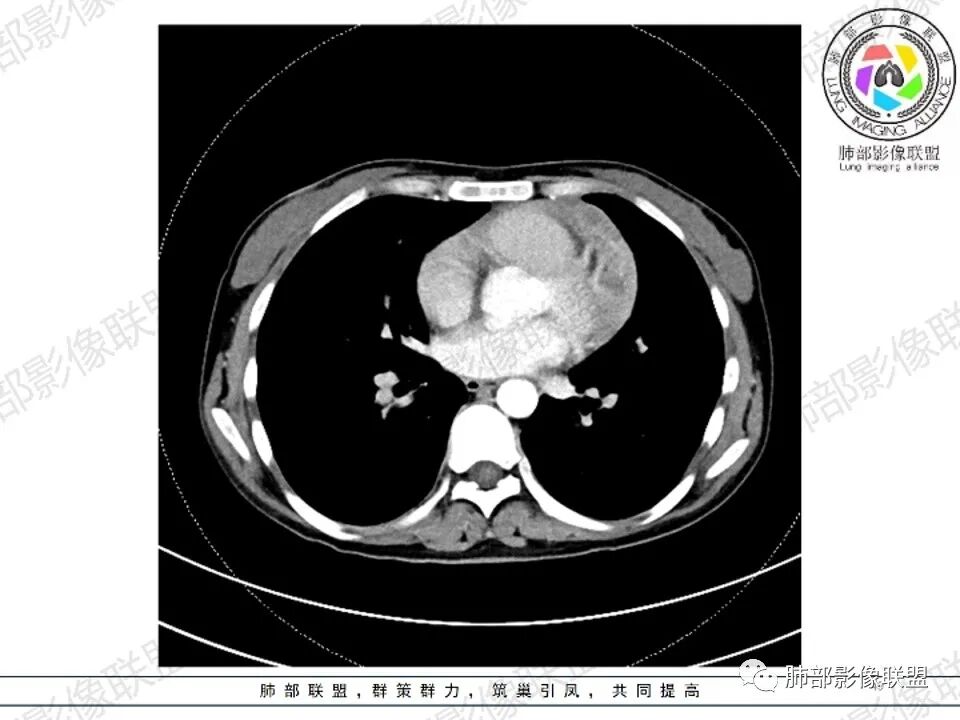

女,27,间断头晕、乏力3年,左眼视物模糊2月。贫血。胸部CT:前纵隔不规则肿块,多结节融合,边界不清,沿主动脉及肺动脉间隙生长,平扫密度欠均匀,增强扫描可见多发低密度坏死,纵隔血管供血穿行,腋窝多发大小不等淋巴结肿大。考虑恶性病变,胸腺癌?肉瘤?淋巴瘤?鉴别胸腺瘤、结节病等。

临床:年轻女性,慢性病程,多系统病变,头晕,贫血,视物模糊。

CT:定位纵膈病变,前中纵隔多发肿块,质软,塑形,密度不均匀,边界清楚。增强不均匀强化,坏死边界清楚,血管漂浮征。双侧腋下多组淋巴结肿大,明显异常强化。

考虑淋巴瘤可能。

2.影像显示前纵隔不规则块状影,依势贴附心脏大血管旁,密度不均,边界不甚清楚,有结节融合感。

3.病灶轻度不均匀强化,可见血管穿行,散在液性低密度区。

双肺门未见肿大淋巴结。

4.双侧腋窝区见增大淋巴结,边界清楚。

1.年轻女性,前纵隔不规则块状影,密度不均,边界不甚清楚,有结节融合感,轻度不均匀强化,可见血管穿行,最常见最符合的无疑是淋巴瘤!